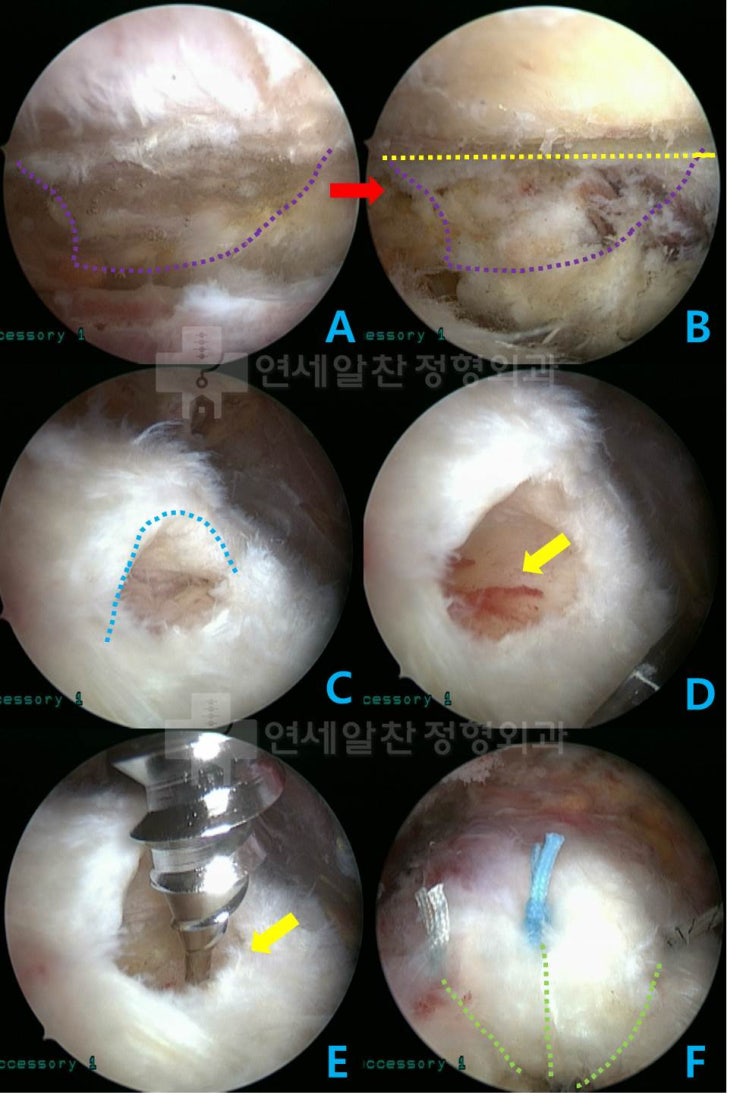

거대한 석회성 건염에서 관절경을 통한 석회 제거술 및 극상근 봉합술(side to side)

43에 여자 환자로 우측 어깨의 극심한 통증을 주소로 내원하였다. 환자는 내원 일주일 전부터 극심한 통증...

2017. 8. 30.